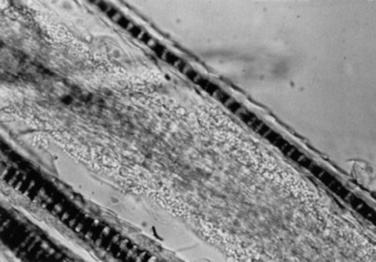

Hair is composed of keratin and is the product of the hair follicle. The hair shaft is the part of the hair that emerges from the skin surface. The hair root is the part of the hair in the follicle. The hair bulb is a knob of epidermal cells that attaches the follicle to the dermal papilla. Both the hair follicle and the shaft have distinct layers. There are two types of hair follicles: simple and compound. A simple hair follicle produces a single hair. A compound hair follicle produces multiple hairs with bundles of hairs sharing a common skin opening and a single follicle down to the level of the sebaceous gland. Below the sebaceous gland the follicle branches so that each hair has its own hair bulb. Horses and cattle have only simple follicles. Goats and sheep have a mixture of simple and compound hair follicles (Fig. 11-7).3,5

image

Fig. 11-7 Longitudinal section of a compound hair follicle.